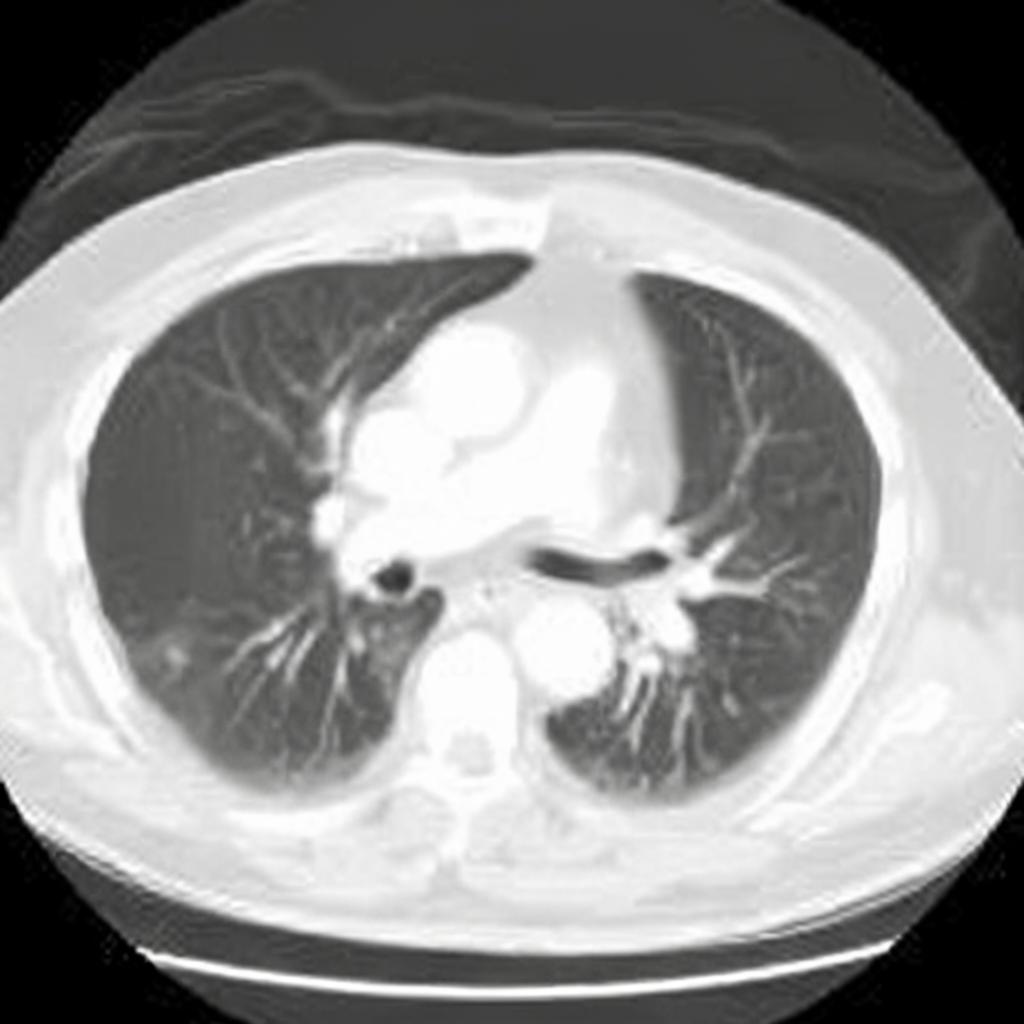

Diffusion models have recently gained significant traction due to their ability to generate high-fidelity and diverse images and videos conditioned on text prompts. In medicine, this application promises to address the critical challenge of data scarcity, a consequence of barriers in data sharing, stringent patient privacy regulations, and disparities in patient population and demographics. By generating realistic and varying medical 2D and 3D images, these models offer a rich, privacy-respecting resource for algorithmic training and research. To this end, we introduce MediSyn, a pair of instruction-tuned text-guided latent diffusion models with the ability to generate high-fidelity and diverse medical 2D and 3D images across specialties and modalities. Through established metrics, we show significant improvement in broad medical image and video synthesis guided by text prompts.

In this work, we focus on the ability of LDMs to generate novel datasets to overcome class imbalances traditionally associated with medical data, and potentially reduce the need for manual annotation of medical 2D and 3D data. We present MediSyn, a pair of text-guided latent diffusion models for broad medical 2D and 3D modality synthesis. To overcome the scarcity of labelled medical data, we leverage a vast corpus of more than 5 million image-caption pairs and 100,000 video-caption pairs collected from the public domain across numerous medical specialties, and integrate comprehensive natural language annotations to develop a pair of versatile diffusion models for the medical domain.

We assembled a set of 5,785,333 medical image-caption pairs, covering 8 specialties and 9 imaging modalities, to train Medisyn’s 2D model. We reserved an additional 1000 image-caption pairs (125 pairs from each specialty) for model evaluation.

| Computerized Tomography (CT) | 1,150,206 |

Our findings demonstrate Medisyn’s remarkable ability to generate high-fidelity and diverse medical images, image sequences and volumetric scans across various medical subspecialties and imaging modalities. Other medical text-driven diffusion models, such as TauPETGen [42] for tau PET images and GenerateCT [43] for chest CT volumes, have proven successful in generating high-quality images that accurately depict anatomical features and clinical conditions. However, these models are constrained to a single imaging modality and anatomical region, thereby restricting their applicability. Moreover, they were trained on relatively small datasets sourced from a limited number of institutions, which could lead to more biased outputs. In contrast, Medisyn, having been trained on one of the largest publicly accessible medical image and video datasets to date, is equipped to synthesize data that cover numerous medical disciplines, population groups, and disease states. Leveraging our two models, we can synthesize new medical datasets as well as augment existing ones, potentially improving a wide array of medical machine learning tools, both general and specialized. Additionally, our models can minimize the need to repeatedly fine-tune on specific datasets for generating different imaging modalities, thus reducing computational costs for academic labs.

In summary, we introduced a pair of text-conditional LDMs trained on an extensive medical image and video dataset covering various medical subspecialties and imaging modalities. By generating high-fidelity and diverse medical 2D and 3D images, Medisyn illustrates the potential for a singular framework to broadly address the challenge of data scarcity in healthcare.